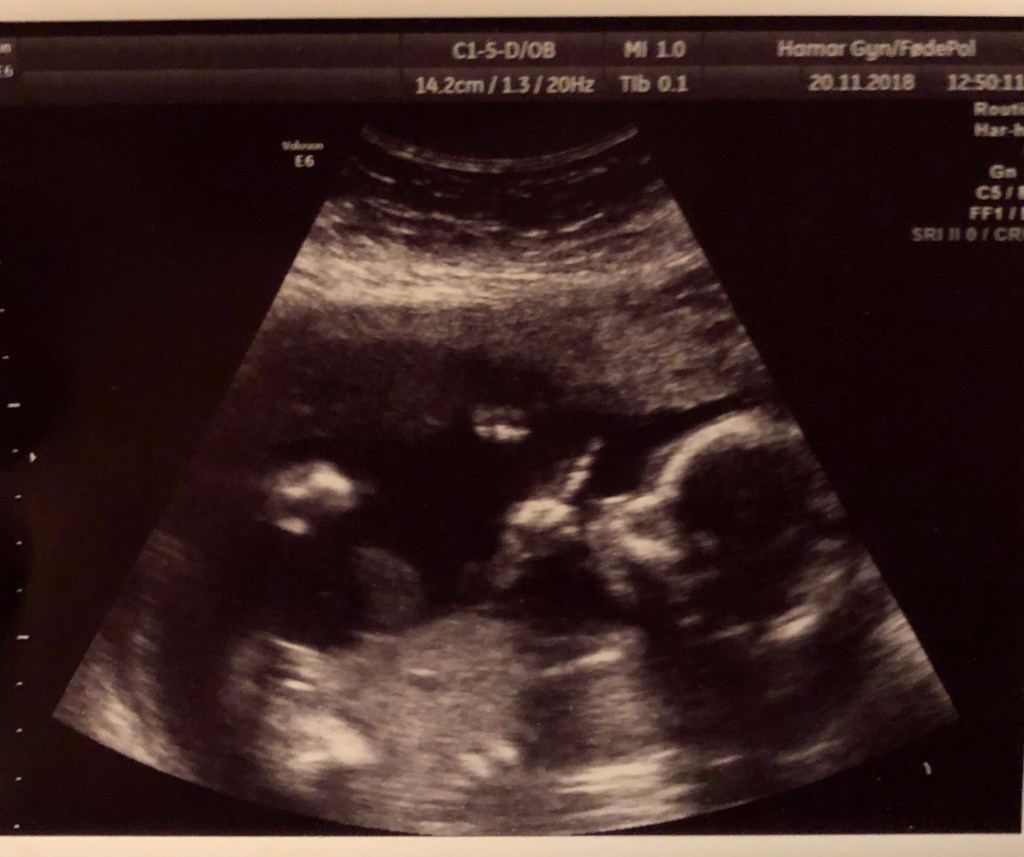

Jordmor přiložila sondu na břicho, který už slušně trčí nahoru i vleže, a byla tam – naše malá Chobotnička! Brečim. A to jsem si slíbila, jak to v pohodě zvládnu. Několikrát koukám na sondu co mi po břiše rejdí a na obrazovku. Fakt že jo, souhlasí to. Oba mlčky zíráme. Naše ruce se našly (přesněji naše zpocené ruce 😀 ) a prostě jen zíráme. Prvních pár okamžiků nám jordmor jen ukazuje miminko a popisuje co kde je, abychom se zorientovali. Ptá se nás, jestli chceme vědět pohlaví. Nechceme. Pak teprve začíná měření. Dostáváme se k tomu, co jsem tvrdila už od začátku. Miminko vypadá o dva týdny menší než kolik vychází podle menstruace. Tadáááá! (Mimochodem, termín podle menstruace byl 26.března, nakonec jsem porodila až o měsíc později.. :-D) Termín se tedy posouvá na 7.dubna a začíná velké focení. Jordmor vyzve Chytrolína, aby si ještě udělal nějaké fotky a video na telefon přímo u ní na monitoru ultrazvuku, kde to bude mít líp vidět, a popisuje mu kde co je. Tiskárna nám plive osm fotek, nemůžu se na ně vynadívat. Prý jestli nám to stačí. Upřímně – mohla bych se dívat celý den. 🙂 Utírám si ručníkem břicho a jordmor si ke mně sedá. Prý tím, že je miminko menší a posunuli jsme termín, mi nabízí ještě jeden ultrazvuk za tři týdny. Zkontrolovat jak miminko roste a líp prohlídnout jeho vnitřní orgány. Rozhodnutí je na nás a já samozřejmě souhlasím, dostáváme tedy nové datum. Ptám se kolik bude chtít za ty fotky. Kouká na mě chudák dost nechápavě, proč prý bych za ně chtěla platit. 😀 Sakra, holt jinej kraj… S Chytrolínem jedeme ještě na oběd, posíláme rodině fotky a do světa oficiální informaci, že v dubnu budeme rodina.

Tři týdny na to jedu, tentokrát už sama, na další kontrolu. Vše se zdá být v pořádku, miminko nám roste jak by mělo, tedy nový termín souhlasí. Přichází opět TA otázka. „Pohlaví znáte?“ „Ne, neznáme.“ „A chcete?“ Sakra! Jsem tu sama. Nemám tu podporu v našem rozhodnutí. A jsem tááááák zvědavá! Kruci, kruci! Všechno mi hrozně rychle běží hlavou. Vydržela bych dělat jakože nic? Ne. Vydrželi bysme udržet tajemství před rodinou? Haha, v sobotu letíme do Čech. Hranice tajemství u Chytrolína překračuje konzumace přesně tří rychlejších piv nebo dva panáky. Blbej nápad. Ale je to tak blízko. Tak snadný to teď zjistit. Sakrááááá! Jordmor opakuje otázku. „Já nevím..“ vypadne ze mě zmateně. Začne se smát. „No rozhodnutí je na vás. Je to vaše miminko.“ Hypnotizuju obrazovku, potřebuju znamení. A přesně o to se v tu chvíli postará Chobotnička. Zdvihá prst. Jordmor reaguje bleskurychle a stíhá udělat fotku. „Tak myslím, že se miminko rozhodlo za vás, že?“ Přesně. Ulevilo se mi. „Jo, necháme si to jako překvapení. Nechci to vědět.“ Začínám se zvedat, jordmor mi podává inkriminovanou fotku. „Chtěla byste fotek víc?“ „A můžu? Minule jsme dostali.“ „To bylo minule. Chcete víc z dneška?“ No to bych byla blbá kdyby ne, že jo? 😀 Tak zpátky nahoru a focení pokračuje. Pak se loučíme s tím, že se možná ještě potkáme u porodu a já se jedu chlubit fotkama za Chytrolínem do práce.